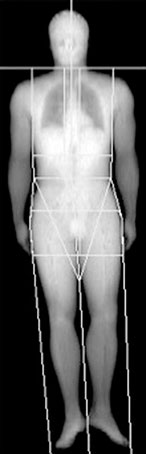

Какой процент вашего организма составляют полезные мышцы, а какой – бесполезный жир? Нашими постоянными помощниками будут замеры объемов тела и процентной доли жира в организме. К концу этой главы у вас появится отправная точка для GPS собственного тела, которая направит вас к цели – реструктуризации 9 кг.

Измерить объемы вашего тела довольно просто – надо лишь вооружиться сантиметровой лентой. Подробности изложены в конце этой главы.

Изображение моего тела, полученное с помощью DEXA.